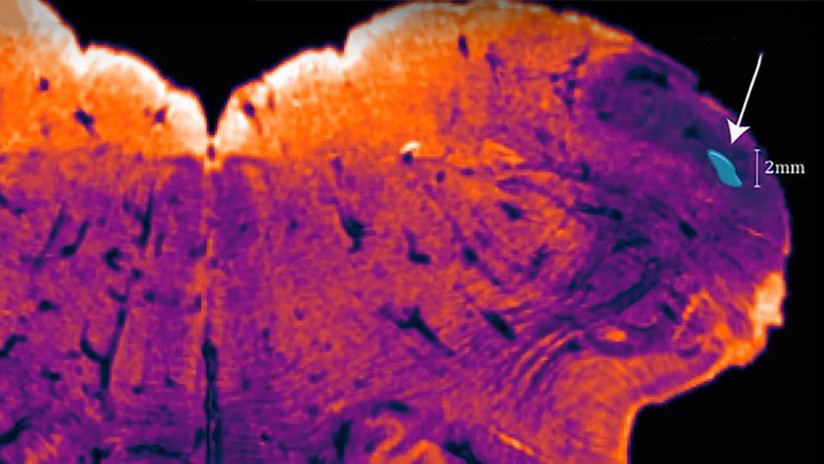

Los efectos que los científicos detectaron al bloquear la autofagia en los hígados de ratones resultaron muy similares a aquellos que se observan en pacientes humanos con la enfermedad de hígado graso no alcohólico (NASH), una patología crónica que incrementa el riesgo de desarrollar cáncer de hígado.

Estos efectos se deben a la acumulación de la proteína Yes-associated (Yap), que, tal y como demuestra este trabajo, promueve cambios en el comportamiento de las células del hígado, lo que incrementa el riesgo de padecer cáncer.

Estos resultados relacionan las alteraciones del metabolismo y la activación de la proteína Yap con el cáncer hepático. El síndrome metabólico es un factor de riesgo importante en las enfermedades crónicas del hígado y el cáncer.